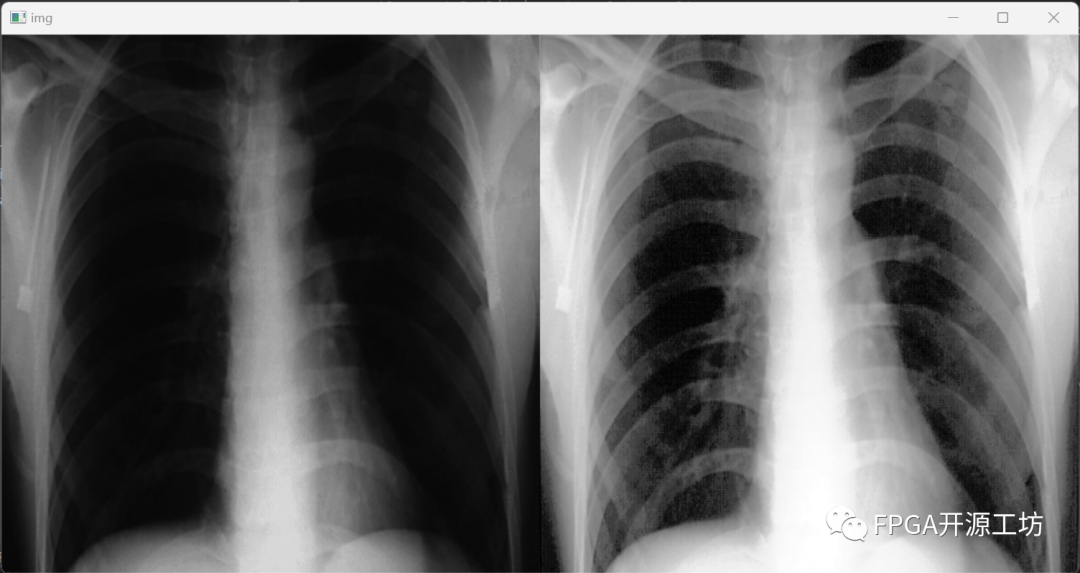

再来看看经过CLAHE算法后的效果。

eebf8ffa-a923-11ee-8b88-92fbcf53809c.png

eee00186-a923-11ee-8b88-92fbcf53809c.png

最左侧为原图,中间为直方图均衡化后的结果,最右侧为CLAHE算法的效果。

从视觉效果上来看,CLAHE算法的效果最为明显。